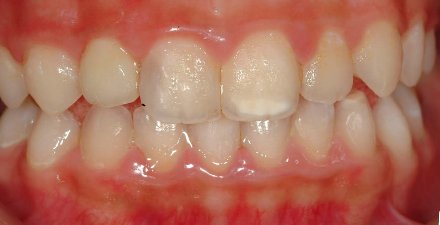

病患高小姐因左上側門齒蛀牙前來本診所求診 , 照數位x 光(圖一)後發現蛀牙處已太靠近神經無法單純以複合樹脂復形 , 需接受完整根管治療後才能進行贋復步驟

圖一 |